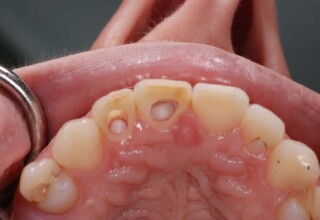

Αποκατάσταση Οπίσθιου Απονευρωμένου Δοντιού με Ανασύσταση Σύνθετης Ρητίνης

Η συνήθης αποκατάσταση ενός απονευρωμένου οπισθίου δοντιού είναι με μια στεφάνη. Ο κύριος λόγος είναι η προληπτική προστασία από κάταγμα και την επακόλουθη εξαγωγή. Σε πολύ συγκεκριμένες περιπτώσεις όπου εξειδικευμένα κριτήρια (κυρίως η ποσότητα της εναπομείνουσας οδοντικής ουσίας) ικανοποιούνται ή όταν η οικονομική δυνατότητα του ασθενή το επιβάλει, μια εκτεταμένη ανασύσταση συνθέτης ρητίνης μπορεί ν’αποκαταστήσει την αισθητική και λειτουργικότητα του δοντιού.